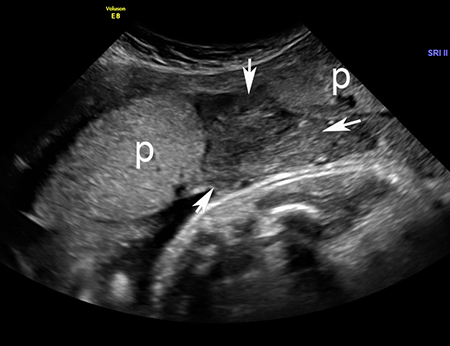

Imagem de ultrassonografia de descolamento da placenta: a placenta normal está marcada com 'p'; área de descolamento indicada por setas brancas

Do acervo de Dr Y Oyelese; usado com permissão